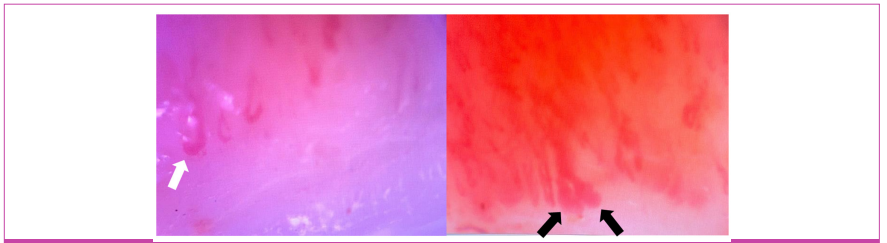

An 88-year-old female patient was referred to the clinic by the dermatology department due to histopathological findings on a skin biopsy consistent with DM. Verbal informed consent was obtained from the patient. She presented with a diffuse red skin rash accompanied by generalized itching. Her medical history did not reveal any significant findings. On physical examination, widespread cutaneous erythema was detected on her upper extremities, lower extremities, and trunk (Figure 1). Additionally, manual muscle testing revealed normal muscle strength in all extremities. The laboratory results were as follows: hemoglobin, 11.6 g/dL; leukocyte count, 5420/mm3 with 6.7% eosinophils; erythrocyte sedimentation rate, 64 mm/h. Normal serum chemistry levels, including creatine kinase 111 (28-168 U/L) with only a slightly elevated lactate dehydrogenase, 329 IU/L (0-246 IU/L). The serological tests for antinuclear antibodies, antibodies to extractable nuclear antigens, antineutrophil cytoplasmic antibodies, rheumatoid factor, and anti-cyclic citrullinated peptide were negative. Additionally, tumor markers, including CEA, CA 19-9, CA 125, α-fetoprotein, and β2-microglobulin, were also negative. A contrastenhanced whole-body computed tomography (head, neck, chest, abdomen, and pelvis) scan performed at baseline revealed a 2 cm polypoid lesion at the gastric cardia. Subsequent upper endoscopy with targeted biopsy demonstrated hyperplastic mucosal changes and chronic gastritis without evidence of intestinal metaplasia or dysplasia. No additional suspicious lesions were identified on imaging. Considering the potential association of erythroderma with hematologic malignancies, a hematology consultation was also requested. However, no hematologic malignancy, including Sézary syndrome, mycosis fungoides, or adult T-cell leukemia/lymphoma, was identified during the evaluation. A skin biopsy showed vacuolar interface dermatitis and dermal mucinosis. A minor salivary gland biopsy was performed due to the patient’s dry mouth and eyes. There was focal sialoadenitis with a focus score ≥1, and the histomorphological findings were compatible with SjS. Capillaroscopy showed disrupted capillary architecture with giant (>50 µm), bushed, and ectatic capillaries (20-50 µm) (Supplementary Figure 1). Although the patient had normal muscle strength and enzyme levels, needle EMG and MRI of the upper and lower extremity muscles were performed to exclude HDM, as the skin biopsy findings were consistent with DM. Based on these imaging and electrophysiological findings, a muscle biopsy was obtained from the deltoid muscle. In the striated muscle biopsy sent, size-shape differences and degeneration and regeneration-like injury findings were observed in the myofibers. Dense perimysial lymphocytes were noted in some areas, and a peri-fascicular atrophylike appearance was observed. In Masson trichrome, the increase in fibrous tissue in the interstitium, indicating a chronic event, was minimal. There were pathological, immature fibers in the perifascicular groups, with neonatal myosin. Additionally, type 2 myofiber atrophy was observed with fast myosin (Supplementary Figure 2). These histopathological findings were evaluated as compatible with DM. We began systemic glucocorticoid therapy with prednisolone (1 mg/kg) and azathioprine. The erythroderma gradually resolved. During the 2-year follow-up of the patient, no loss of muscle strength or malignancy developed.